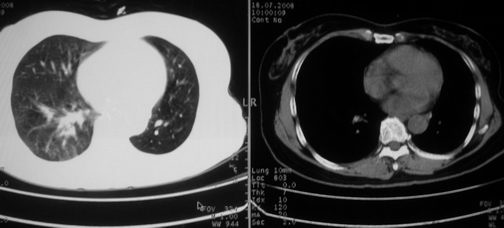

以下是引用李衡钧在2008-7-24 14:24:00的发言:[br]左侧胸廓变小,左肺上叶见大面积致密阴影,其内有空洞及不规则钙化。上纵隔略向左移位,上肺胸膜增厚。左肺门及纵隔淋巴结增大。右肺见散在的致密结节影。[br]印象:继发性肺结核。